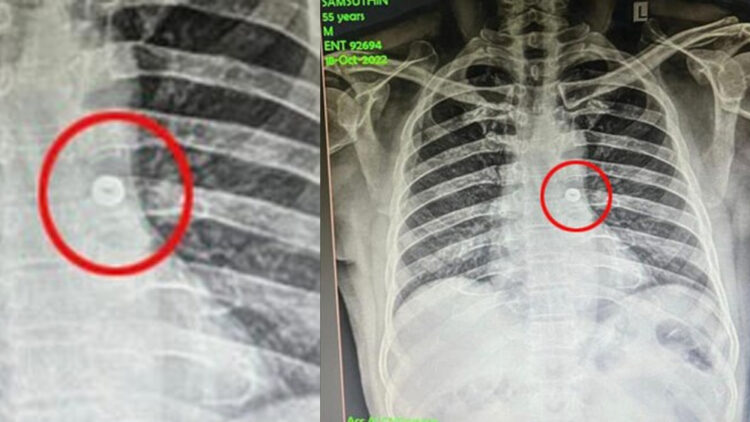

നട്ട് ഉള്ളിൽ പോയതോടെ ഷംസുദ്ദീൻ ചുമയ്ക്കാൻ ആരംഭിച്ചു. പിന്നാലെ ശ്വാസം എടുക്കാൻ ബുദ്ധിമുട്ട് അനുഭവിച്ചു. ഇതോടെ ഒപ്പം ഉണ്ടായിരുന്നവർ ഇയാളെ ആശുപത്രിയിൽ എത്തിക്കുകയായിരുന്നു. തുടർന്ന് ഷംസുദ്ദീനെ ഓട്ടോറൈനോലാറിംഗോളജി വിഭാഗത്തിൽ പ്രവേശിപ്പിച്ചു. നെഞ്ചിന്റെ എക്സ്-റേ എടുത്തപ്പോൾ ഇയാൾ വിഴുങ്ങിയ നട്ട് ശ്വാസനാളത്തിൽ കുടുങ്ങി ഇടതു ശ്വാസകോശത്തിലേക്ക് പോകുന്നതായി ഡോക്ടർമാർ കണ്ടെത്തി.

തുടർന്ന്, ഓട്ടോറൈനോലാറിംഗോളജി വിഭാഗം മേധാവി ഡോക്ടർ ശരവണൻ, അനസ്തേഷ്യോളജി വിഭാഗത്തിലെ അലിസുൽത്താൻ, മണിമൊഴി, സെൽവൻ, മദനഗോപാലൻ എന്നിവരടങ്ങുന്ന ഡോക്ടർമാരുടെ സംഘം എൻഡോട്രാഷ്യൽ ഉപകരണം ഉപയോഗിച്ച് ശസ്ത്രിക്രിയ നടത്തി. ഇതിലൂടെ ഷംസുദിൻ വിഴുങ്ങിയ ഇരുമ്പ് നട്ട് വിജയകരമായി പുറത്തെടുക്കുകയായിരുന്നു.